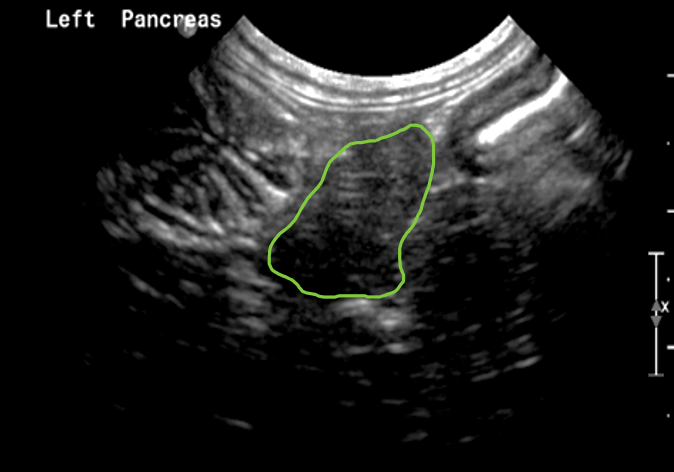

The Left Limb of Pancreas

Midline long axis section of the patient – short axis of the gastric body and left limb of pancreas lie ventral to spleno-portal vein and cranial to the transverse colon in short axis

- Once you have the stomach and colon visible, the third landmark to search for is the spleno-portal vein, which with careful probe movement will become visible in its long axis in the far field. These 3 landmarks form a triangle, in the middle of which will be the left limb of the pancreas in it’s transverse/short axis. The left limb of the pancreas therefore lies caudal to the greater curvature of the stomach, cranial to the transverse colon and ventral to the spleno-portal vein. The spleen can often be seen in the near field and can be used as an acoustic window in some patients.

The short axis section of the left limb of pancreas seen caudal to the contracted stomach (cartwheel shape on the left of the screen) and cranial to the colon (seen with hyperechoic lumen. A section of the spleno-portal vein is just visible immediately dorsal to the pancreas